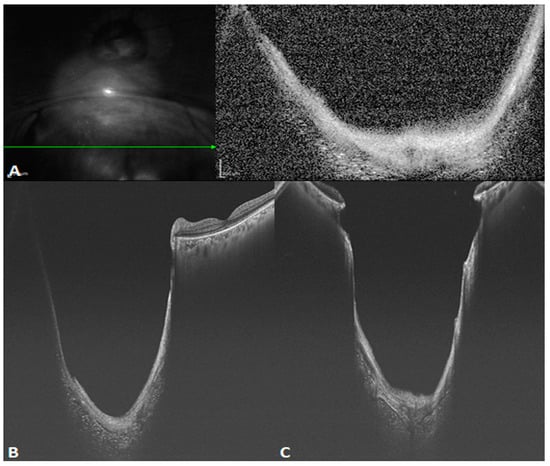

facile structure, which efficiently restrains common mode noise. As a consequence, even at the same scanning speed, SS-OCT yields a better sensitivity and higher image signal-to-noise ratio (SNR) than SD-OCT, even in the case of weak OCT signals due to refractive medium turbidity, such as that caused by cataracts or vitreous hemorrhage. This latter shortcoming is overcome by the penetration depth and sensitivity of the technique. Figure 2 reveals the difference between SD- and SS-OCT in acquiring retinal images from a patient with refractive medium turbidity. SS-OCT is better able to display the characteristics of tissue structures, improving clinical diagnosis.

Figure 2.

B-scan images of a patient with refractive medium turbidity and a huge choroidal coloboma. (A) Spectral-domain OCT (SD-OCT) image showing a part of the coloboma, but the structure is blurry (The green arrow in the left image indicated the orientation of B scan OCT in the right image). (B) An oblique SS-OCT scan of the same choroidal coloboma and the macular area. Even the posterior scleral space can be visualized. (C) A B-scan SS-OCT image with a range of 20 × 20 mm showing the full extent of the choroidal coloboma.